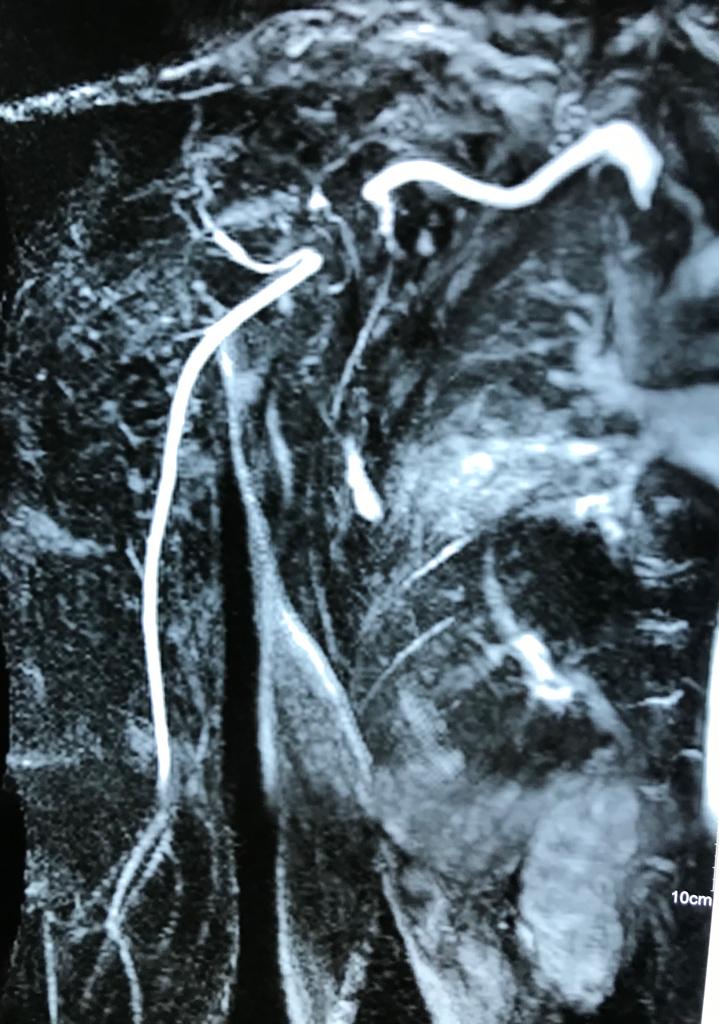

Angioresonancia periférica (miembro superior derecho).

Pacientes con luzación glehumeral anterior y fractura diafisiaria del humero, de un mes de evolución. Se complica con una oclusión de un segmento de la arteria subclavia-axilar, secundaria a trombosis.

Las lesiones de vasculares asociadas a fracturas y luxaciones del hombro son poco frecuentes, aunque potencialmente muy graves por lo que requieren un diagnóstico y actuación urgentes. Debido a la proximidad anatómica, pueden coexistir signos de compromiso de nervios mediano, radial y cubital.